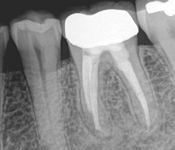

Pictured: Necrosis and 3 Year Recall with Complete Root Formation after Revascularization

Our patient developed necrosis of tooth #9 caused by intrusive luxation. We opted to treat with revascularization with triple antibiotic and MTA. In our 3 year recall, the patient had achieved complete root formation.